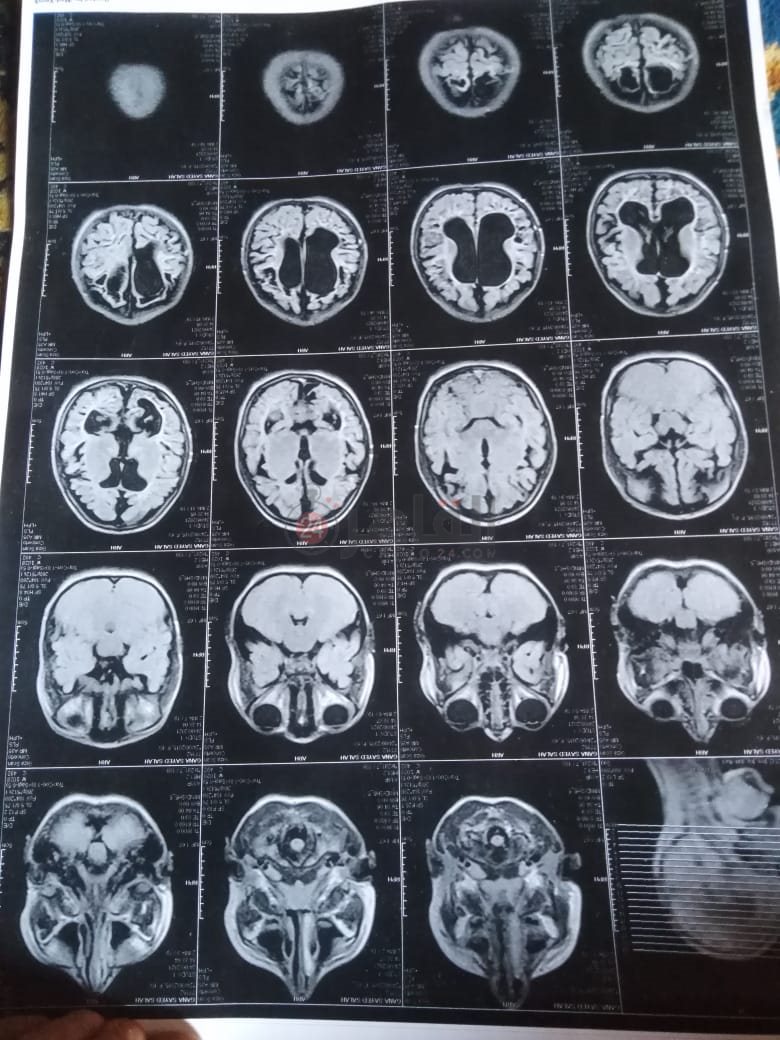

من جانبه، قال صلاح سيد، والد الطفلة جنى صلاح، إن ابنته تعاني من ضمور في المخ منذ ولادتها، نتيجة خطأ طبي، أدى إلى نقص كبير في الأكسجين لديها.

وأضاف في تصريحات خاصة لـ "القاهرة 24": "جنى تبلغ من العمر 6 سنوات، لا تستطيع المشي أو الوقوف على قدميها، نتيجة إصابتها بضمور في المخ منذ ولادتها".

وتابع: "مكنتش بتتحرك خالص، وجسمها طري، روحت كشفت عليها، وعملت أشعة وتحاليل كتير، أتأكدنا إصابتها بضمور في المخ"، مضيفًا:" مش بتعرف تأكل احنا اللي بنأكلها، هي عقلها كويس لكن مش بتتحرك ولا تتكلم".